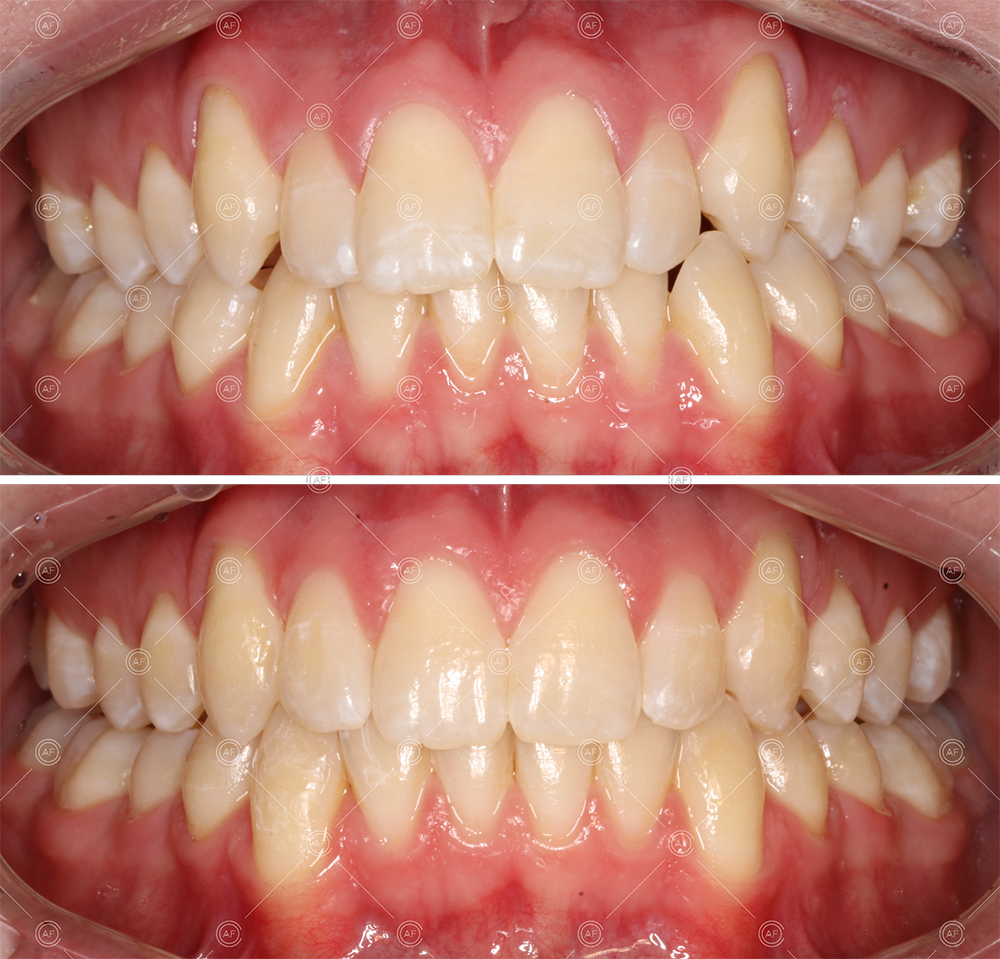

This patient (MH) began her active orthodontic treatment in October 2019 at almost 13 years old. She was unhappy with the appearance of her upper and lower teeth, and especially concerned about the unsightly nature of the high and buccally positioned upper left canine.

about this case…MH presented with class 1 incisors on the class 1 skeletal base with a slightly increased vertical proportion. She had severe crowding in the upper arch and moderate crowding in the lower. Due to the crowding in the lower arch, the lower centre line was off to the left by 2mm.

MH debonded in December 2020, with overall treatment time of around 14 months.

She was provided with upper and lower vacuum form retainers, and asked to wear these every night for the first year, and alternate nights for the second year onwards, indefinitely for as long as she wanted her teeth to remain straight. High quality finish was maintained at one year post-debond.